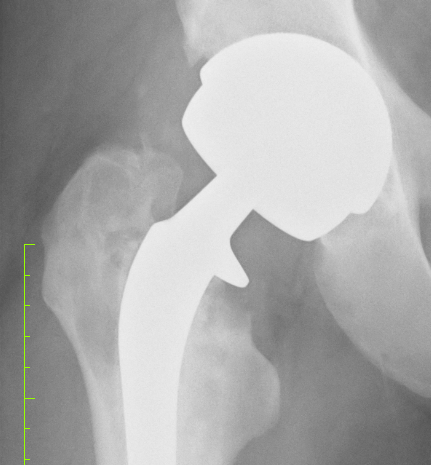

So – the procedure will be something like this:

- Open up the hip – have a nice handy road map (read scar) from the last operation.

- Split the femur – effectively take the top off – like a convertible roof on a sports car!

- Dig out the femoral prosthesis and all the excess glue from the last surgery as the original surgeon did not use a glue restriction cup.

- Wire the femur back together again.

- Then most likely press-fit the revision femoral stem which will be a little longer than the stem used first time round. And it will be flanged – a Zimmer implant.

Finished job with the wires should look a little like this:

Then the next step will be to dig out the acetabular cup – which is press fitted in – despite the original surgeon’s notes saying it was cemented!!!

Most likely there will be a need for a bone graft or some form of packing & screws for the new cup.

Then in goes the ceramic insert and femoral head – presto; a new man!